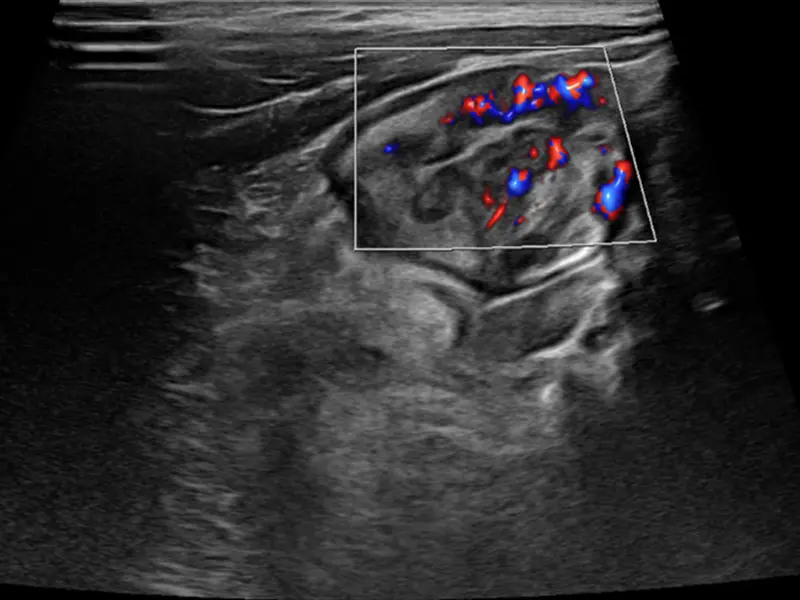

The end of the small bowel called the terminal ileum, which is inflamed in a 7-year-old boy before he begins a new therapy for his Crohn’s disease.